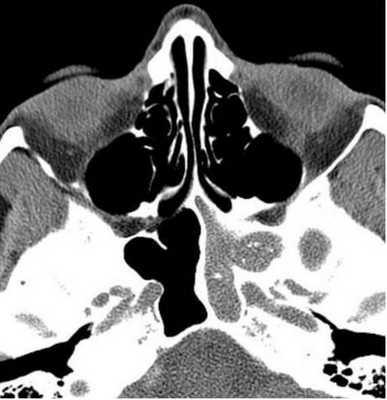

Пиоцеле (скопление гноя) задних клеток решетчатой кости